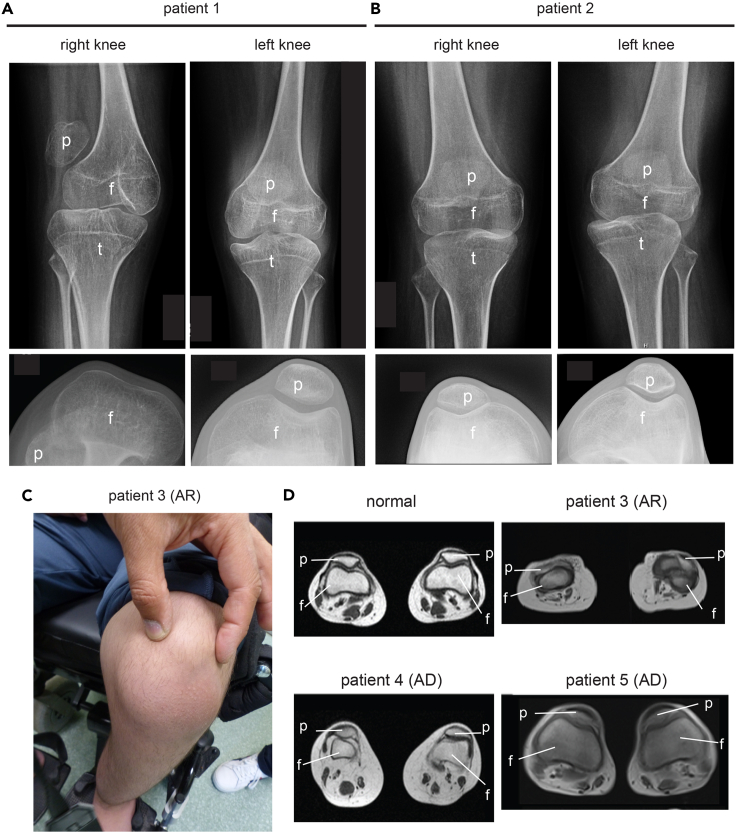

Our analysis highlights the importance of collagen XII for the organization of patella-tendon-ligament unit, but little is known about consequences of collagen XII deficiency for the knee joint organization in human patients. We therefore revisited the clinical files of two siblings (patient 1, patient 2) with a homozygous splicing mutation of COL12A1 (c. 8006 + 1G>A). This mutation causes a skipping of exon 50 and a premature stop codon formation in exon 51, leading to a loss function because of truncated collagen XII translation without collagen domains.8 In early childhood they had very unstable knees with patellar subluxations in both knees (Figures 6A and 6B). The X-ray analysis revealed for one sibling (patient 1) a complete absence of the femoral trochlear grooves, while these were less pronounced in the other (Figure 6A, left, lower panel). Moreover, the patella could not be kept in the proper position because of the missing femoral trochlear groove, was not well centered (upper panel) and located on the side of knee. In addition, we identified a novel homozygous mutation (c.5230 + 1G>A) in the COL12A1 gene leading to recessive loss of collagen XII in one patient (patient 3). This patient presented with an autosomal recessive form of the collagen XII-associated myopathy without progressive muscle weakness, but with a remarkably small and dislocated patella and reduced femoral trochlear groove (Figures 6C and 6D). Finally, we revisited the MRI data of two patients (mother and daughter, patient 4, patient 5) with a heterozygous mutation (c.G8357A) in COL12A1 gene causing a substitution of a conserved glycine residue in the Gly-X-Y motif of the triple helical domain of collagen XII.6 Here, a flattened trochlear groove (Figure 6D), as well as joint hyperlaxity, jaw and hip dislocation was detected. The daughter’s kneecaps were hypermobile and medially displaced upon adopting a standing position. Hence, malformed femoral trochlear grooves, patellar subluxation and joint destabilization are often clinical features in patients with recessive loss or heterozygous mutations of COL12A1 gene.

Figure 6.

X-ray analysis of the human patella/knee region

(A and B) The knees of two COL12A1 deficient siblings (1 + 2) with mutation of COL12A1 c.8006 + 1G>A8 were investigated by X-ray analysis. Frontal views reveal the localization of the patella (p), tibia (t) and femur (f) (upper panel). X-ray analysis of the bent knees to visualize the femoral groove and the patella (lower panel).

(C) Frontal view – knee from a homozygous patient (3) with an autosomal recessive mutation of COL12A1: c.5230 + 1G>A. Dislocation of the patella is indicated.

(D) Representative MRI-images of the malformed femoral groove in the novel patient (3) and in previously described autosomal dominant patients with mutation of COL12A1: G8357A (4 and 5) (Family 1a and 1b6) compared to normal. The position of femur (f) and patella (p) is indicated.